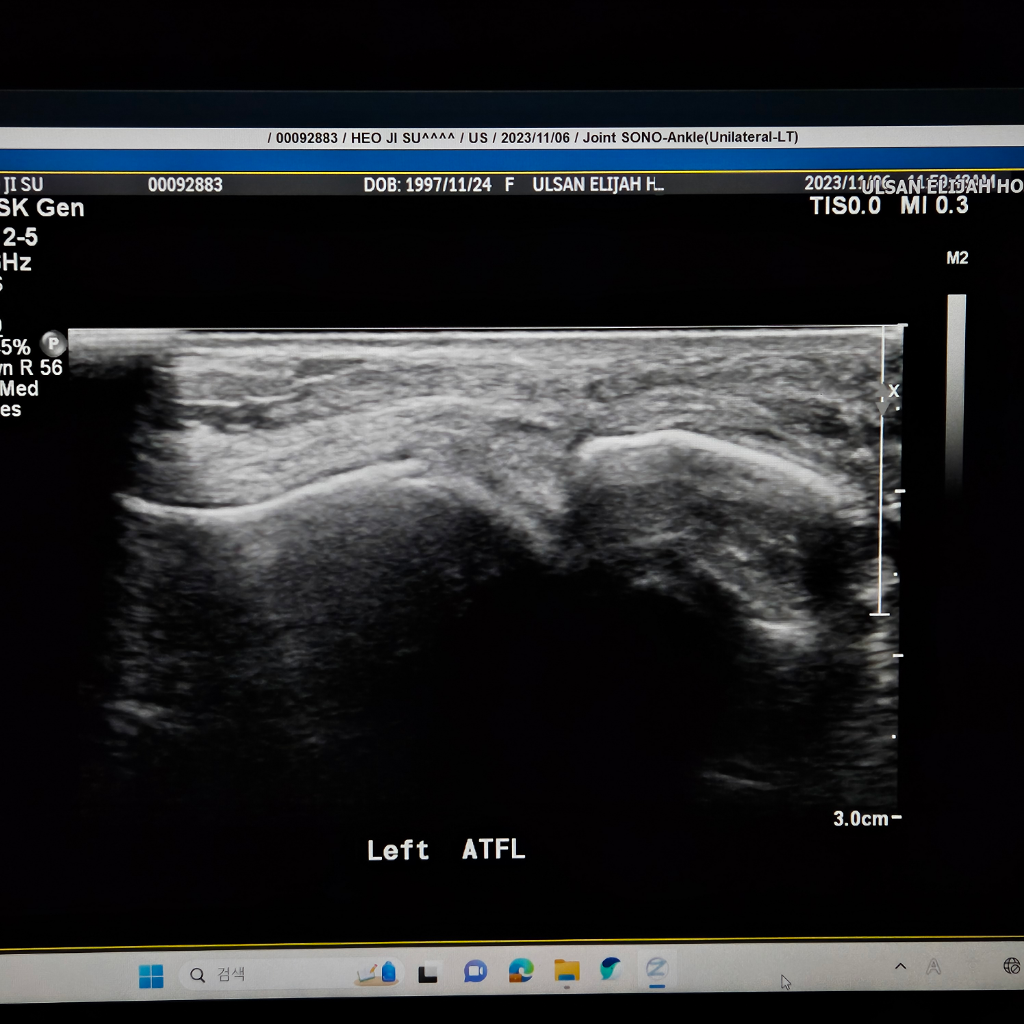

발을삐어서 병원을 갔는데 인대가 파열됬다는데 맞는지요?

발을 삐어서 병원을 갔는데 첨에 걸을때 넘아파서 못걸을정도 였습니다. 복숭아뼈 주위도 부워있었고

초음빠도 찍었습니다. 초음파에서 인대가 끈어졌다는데

끈어진게 맞나요? 첨에 수술 예기 하더니 아직 젊으니 반깁스 하고 일주일 두고보자고했습니다.

• 3번 째 사진

초음파는 실시간으로 발목을 움직여보면서 찍습니다.

검사자가 가장잘 판단을 내릴수 있습니다.

해당병원에 재문의해보세요.